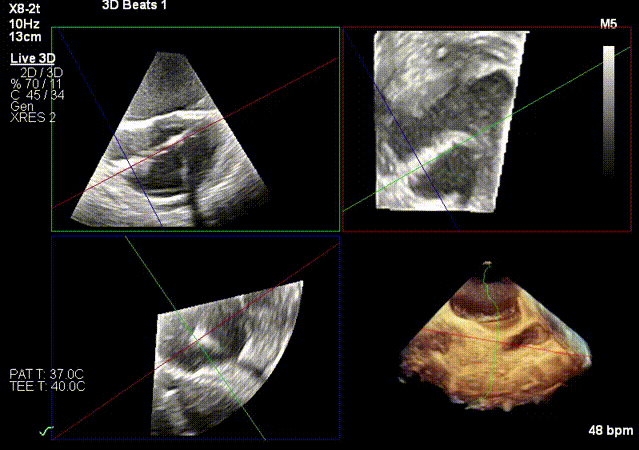

实时3D